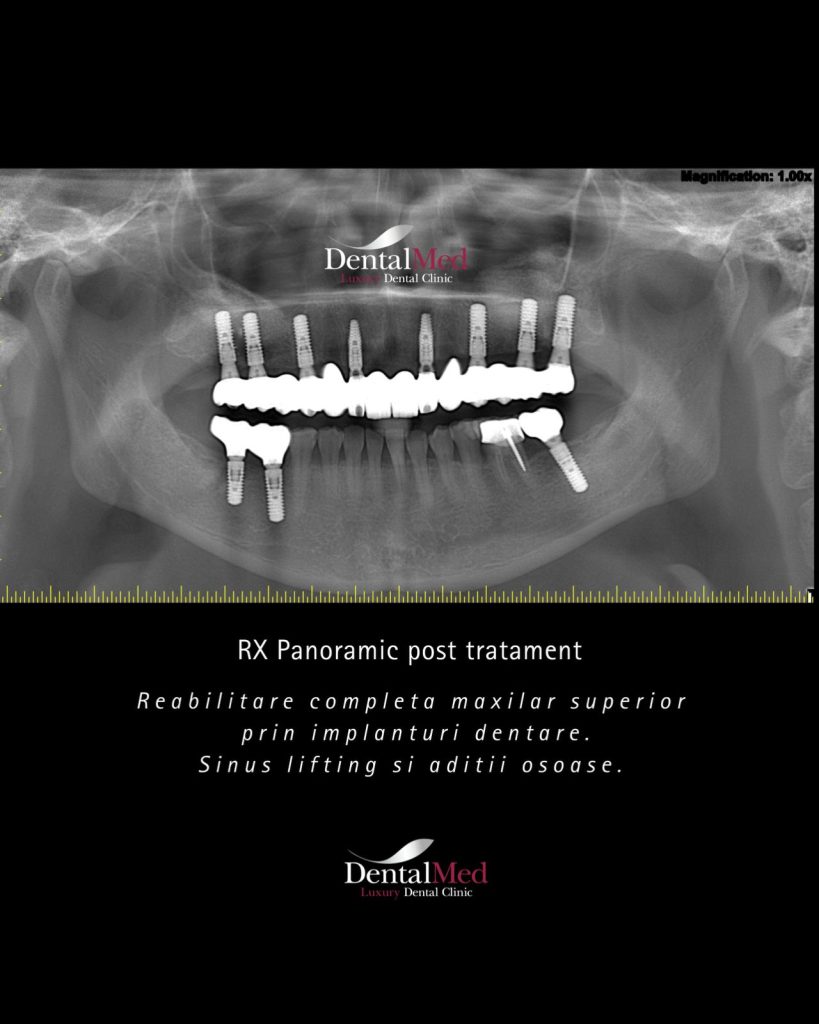

Procedura de sinus lifting se efectueaza de obicei sub anestezie locala, fiind complet nedureroasa. Medicul realizeaza o mica deschidere in osul maxilar, ridica delicat membrana sinusului si introduce materialul de aditie osoasa (os natural sau artificial). Acest material va stimula formarea de os nou, creand o fundatie solida pentru implantul dentar.

Este important de precizat ca sinus liftul poate avea loc separat de inserarea implantului (cu aproximativ 6 luni inainte, pentru ca osul sa se formeze) sau acestea pot fi inserate impreuna (situatie in care se asteapta aproximativ 8 luni pana la momentul realizarii lucrarii definitive).

- Sinus lift separat de implant – materialul de aditie este introdus si se lasa aproximativ 6 luni pentru formarea osului nou. Ulterior, se poate insera implantul;

- Sinus lift concomitent cu implantul dentar – atunci cand exista o cantitate minima de os, se pot realiza ambele proceduri simultan. In acest caz, timpul de asteptare pana la lucrarea finala este de circa 8 luni.